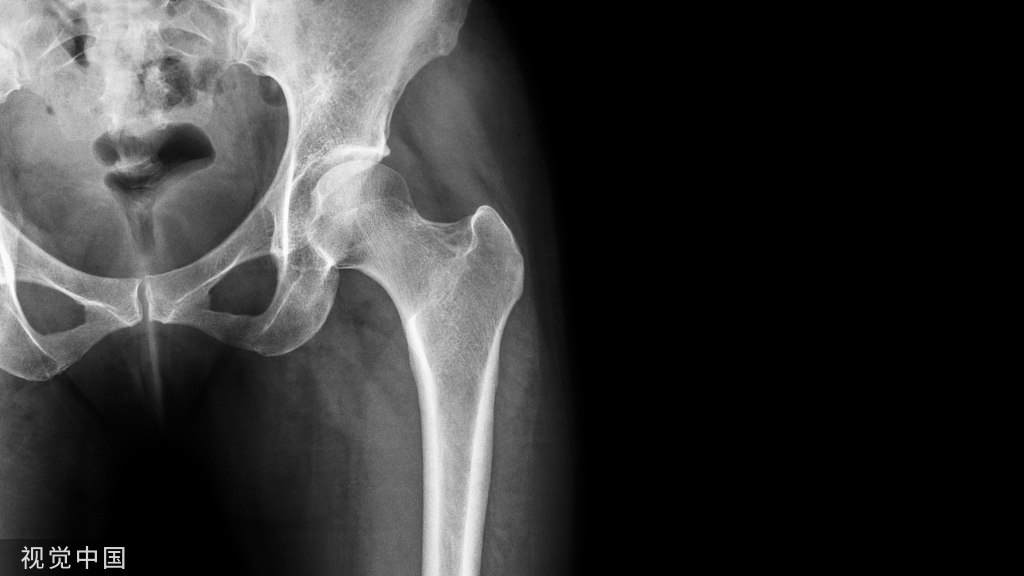

全髋半髋置换术中,由于骨水泥的植入使患者出现一过性或明显的低血压和PaO2的降低,并使约0.6-1%的病人出现心搏骤停。此类特殊的症状称为骨水泥植入综合征。

是一种少见但非常严重的骨科手术并发症,常发生于髋或膝关节置换手术时骨水泥假体植入过程中。

Javad Parvizi 等对13个在进行骨水泥髋关节成型手术中死亡的病人尸检发现,11个可见肺部骨髓微栓塞(左图1),3个可见聚甲基丙烯酸甲酯颗粒(右图2)。